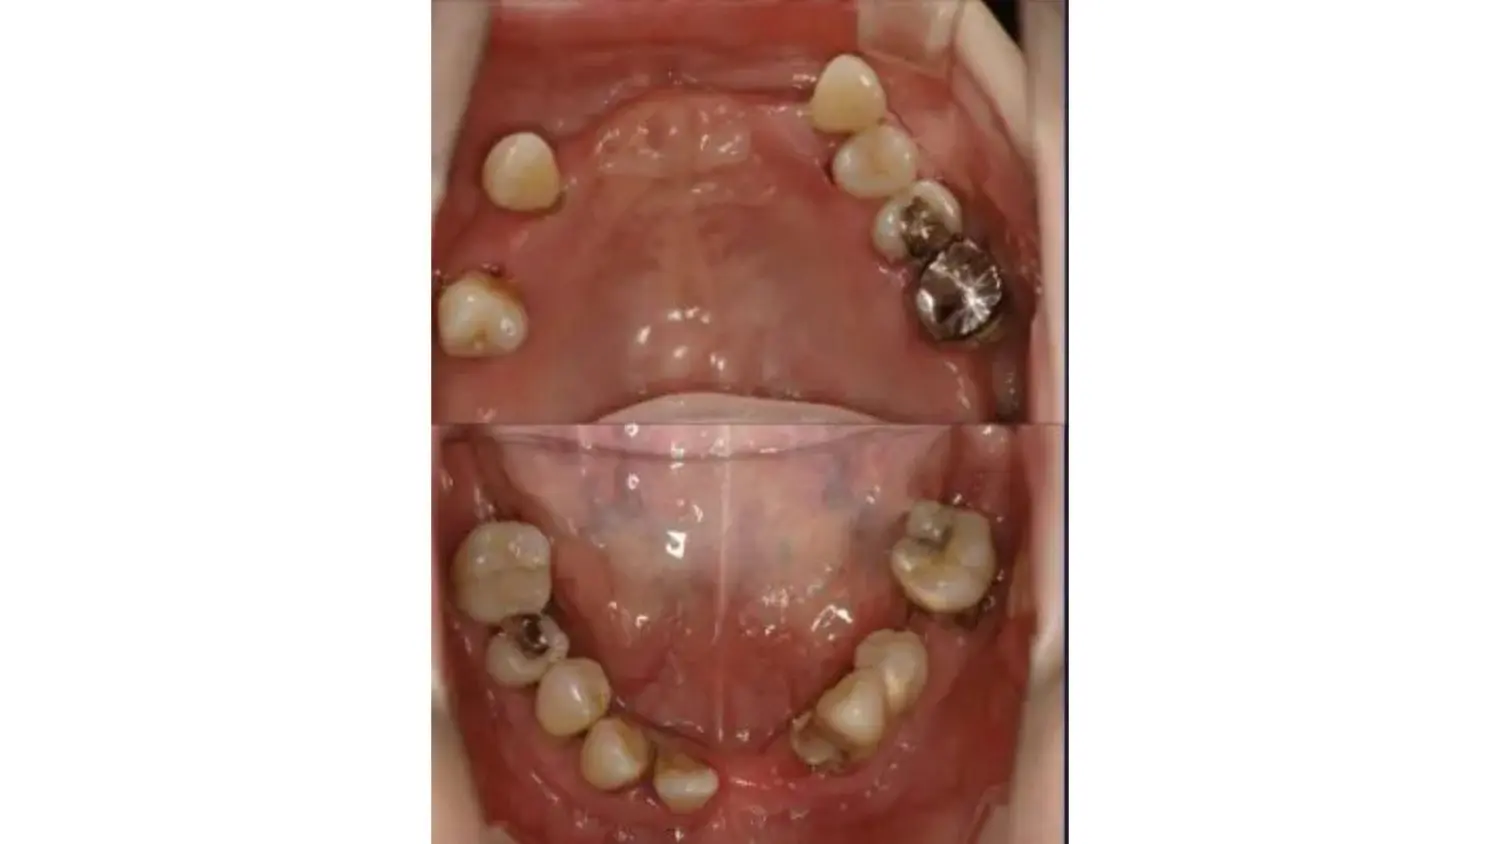

| 主訴 | 全顎治療希望、奥の歯茎から血が出る、綺麗で噛めるようになりたい |

| 治療内容 | 全顎的に歯周病、歯列不正が認められるため、歯周外科を含む歯周治療、矯正治療、インプラント治療、セラミックによる補綴治療後メインテナンスに移行 |

| 治療費 | 2,930,000円(税込)(インプラントすべて含む) |

| 治療期間 | 2年6ヶ月 |

| 治療回数 | 96回 |

| 想定されたリスク | 歯周病の再発、食いしばり(パラファンクション)によるセラミックの破折、歯の破折 |